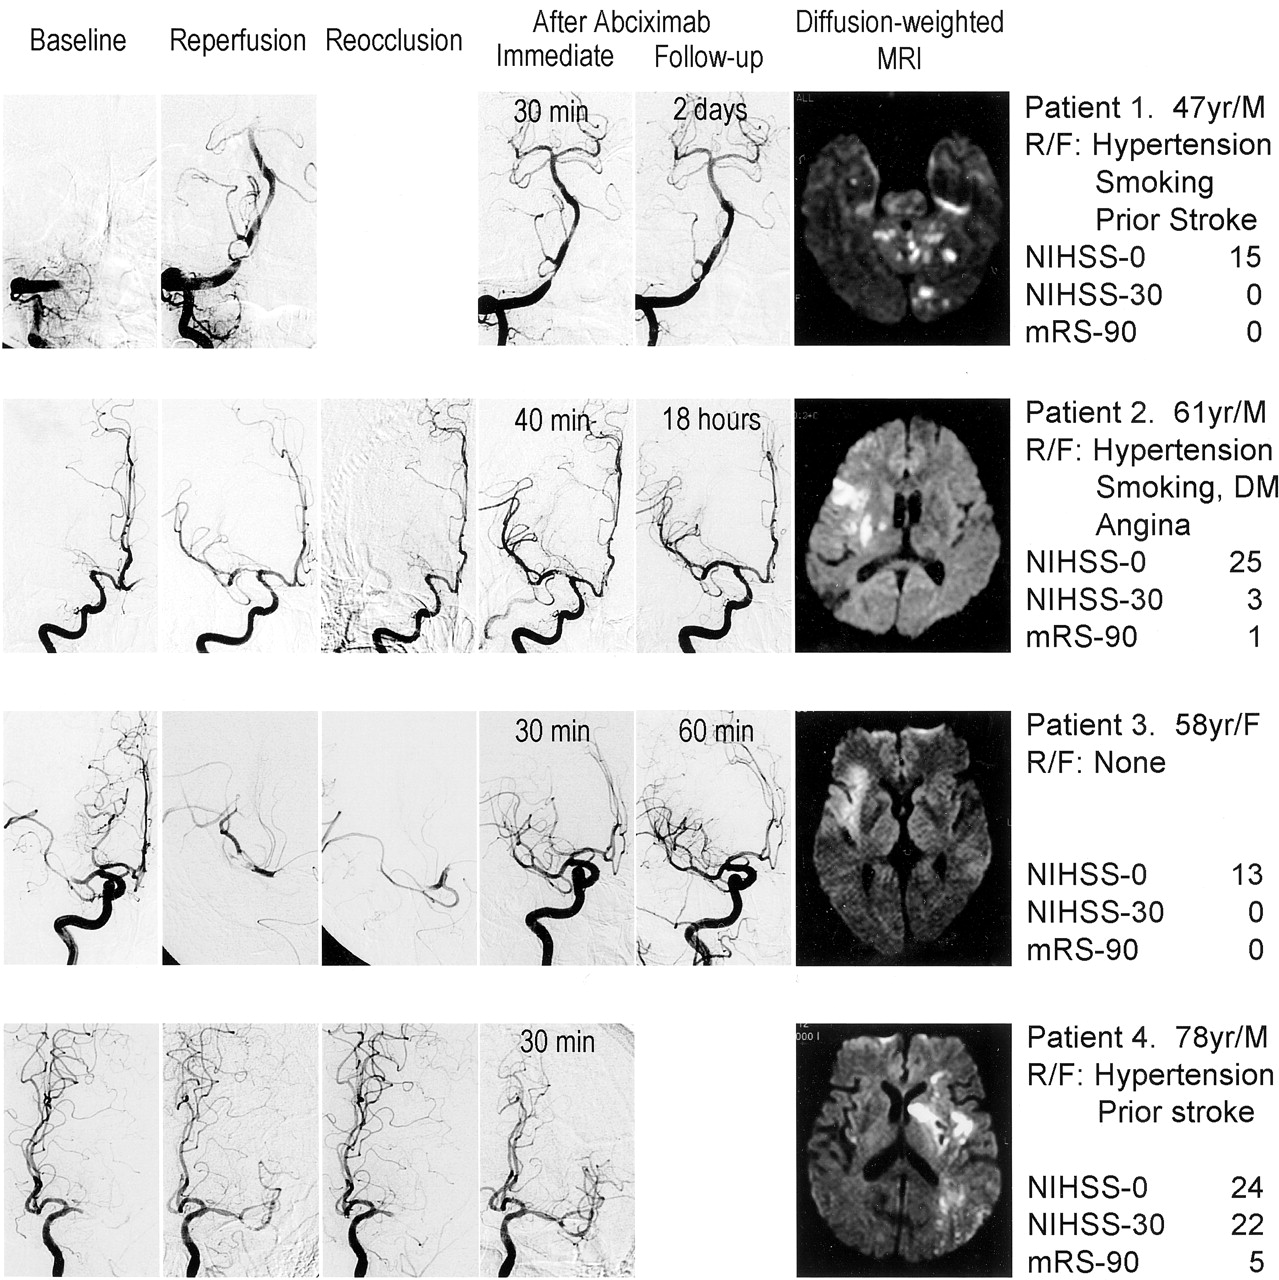

最初的血管再通达到18例(62%;TIMI 3 9和TIMI 2 9)但不成功的11个患者在3和TIMI 0 (TIMI 1 8)。平均基线NIH卒中量表分数18日在患者成功再通,在那些没有22。百分之七十二的患者成功再通和27%的不成功再通有一个夫人- 90≤2 (p由Mann-Whitney = 0.027U测试)。Reocclusion发生18例患者中4例(22%)与最初的血管再通。三个reocclusion患者理想(TIMI 2)流。reoccluded动脉包括MCA在三个病人,一个病人的VBA (图1)。所有reocclusion患者联合溶栓治疗。

图1所示。串行血管造影显示初始溶栓后血管再通和随后的reocclusion疗法。reoccluded动脉abciximab灌注后重新开放。有一个小出血病人的左基底神经节4。病人的血管造影在reocclusion用时2。DM =糖尿病;夫人- 90 =改良Rankin得分在90天;在基线NIHSS-0 = NIH卒中量表;在30天NIHSS-30 = NIH卒中量表;R / F =风险因素。

系统管理abciximab与血栓的溶解后30到40分钟内所有reocclusion患者丸。持久性的动脉血管造影前三了病人在2天内。动脉开放如此广泛,没有残余狭窄被发现在两个病人,和一个病人的狭窄得多改善。一个病人有一个小出血不是与神经功能恶化有关。血管再通伴随着显著的临床改善三个病人(见图1)。